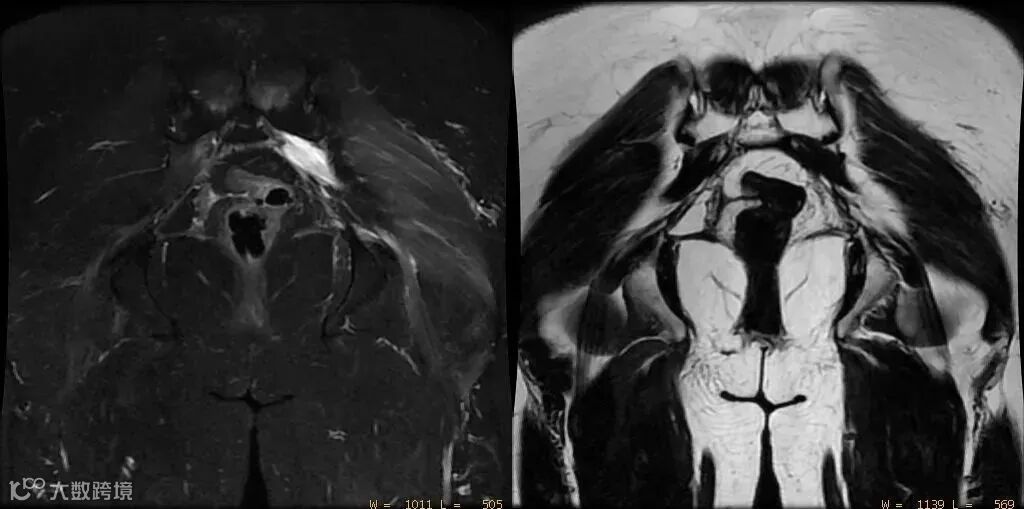

③伪影

- 化学位移伪影

:位移像素数 = 水脂频差 / 像素带宽 - 扩散加权成像(DWI)

:相位编码方向伪影取决于回波间隙(ESP) - 磁敏感伪影

:带宽↑ → 伪影↓;场强↑ → 伪影↑ 可参考:MRI中那些实用的数值与计算方法!